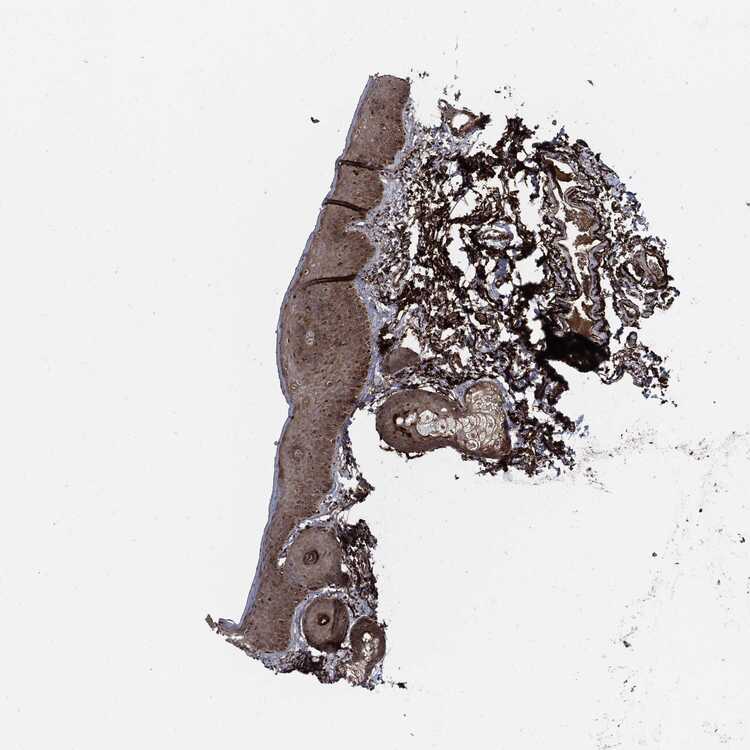

VAGINA - Antibody stainingi

Antibody staining in the annotated cell types in the current human tissue is reported as not detected, low, medium, or high, based on conventional immunohistochemistry profiling in selected tissues. This score is based on the combination of the staining intensity and fraction of stained cells.

Each image is clickable and will lead to virtual microscopy that enables deeper exploration of all samples and also displays staining intensity scores, fraction scores and subcellular localization as well as patient and tissue information for each sample.

Antibody HPA000572Antibody CAB016253Antibody CAB080180

Squamous epithelial cells Not detectedNot detectedMedium